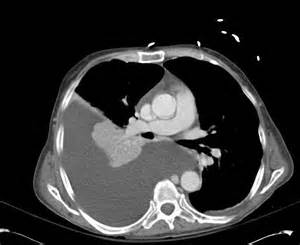

KT – plevral xəstəlikləri dəqiqləşdirən müayinədir.

Plevrada mayeni rentgen göstərə bilər. Qabırğa-diafraqma cibinin düzləşməsi, plevrada homogen kölgəlik, Damuaze xətti mayenin rentgenoloji əlamətləridir. Qabırğa-diafraqma xəttinin düzləşməsi plevrada ən azı 250 ml mayenin olduğunu göstərir. Lakin, mayeni görmək üçün ən həssas müayinə USM-dir.

Plevral mayenin biokimyəvi (protein, albumin, qlükoza, LDH, pH), mikrobioloji (qram boyama, kültür) və sitoloji müayinələri əksər hallarda mənşəyi və xarakteri barədə yetərli məlumat verə bilir. Klassik olaraq plevral maye transudat və eksudat olaraq iki yerə bölünür. Ürək, qaraciyər və böyrək yetməzliklərində adətən transudativ xarakterlı mayelər olur. Eksudativ maye isə adətən iltihabi və bədxassəli xəstəliklərdə daha çox rast gəlir. Bu xəstəliklərin müəyyənləşdirilməsində isə KT faydalıdır.

Eksudativ plevral mayelərdə önəmli məsələlərdən biri irinli iltihabın olub-olmamasıdır. Mayedə irintörədici mikrobların tapılması və ya pH-ın 7,2-dən aşağı olması irinli iltihaba xarakterikdir. Belə hallarda iltihabın əsas səbəbini də axtarmaq lazımdır. Aparılan ikinci pillə müayinələrə baxmayaraq səbəb tapılmırsa üçüncü pillə müayinələrinə üz tutmaq lazım gəlir (Şəkil 3).